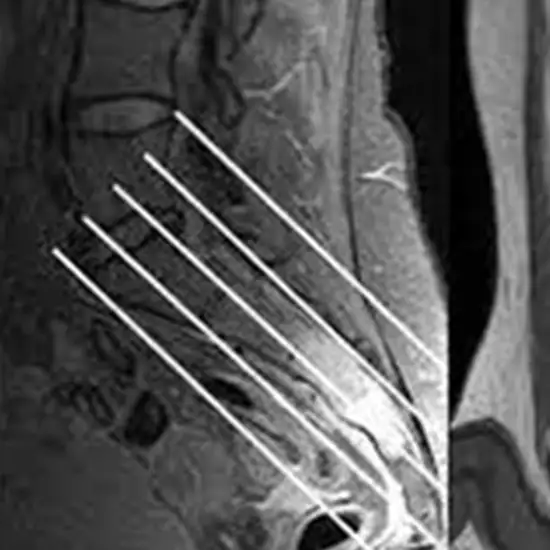

The MRI Spine Sacrum and Coccyx test look at the sacrum and the tail bone (coccyx).

• MRI of the sacrum and coccyx can help evaluate sacroiliac (SI) joint problems, which connect the lower spine to the pelvis.